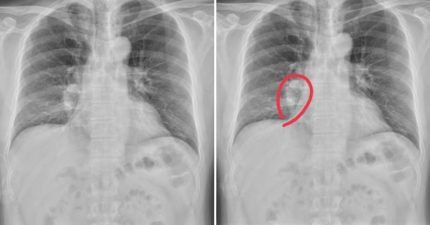

每天打10次嗝!正妹就醫才知罹「癌症第3期」

May 3, 2023

世界, 知識